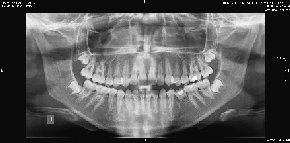

• Panorámica digital

Algunos ejemplos de imágenes digitales

Pulse en las imágenes para ver la ampliación